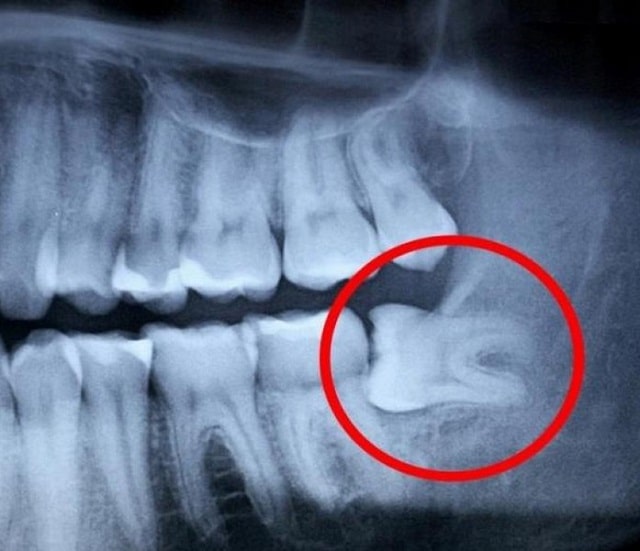

Визуально ретинированный зуб может быть незаметен. Пациенты чаще жалуются на периодическую боль, отек, ощущение давления или воспаление десны. Важно вовремя провести рентгенографию, чтобы определить точное положение зуба и степень его ретенции.

Ретенция бывает:

- Полная — зуб полностью скрыт под десной и костной тканью.

- Частичная — зуб частично прорезался, но не до конца.